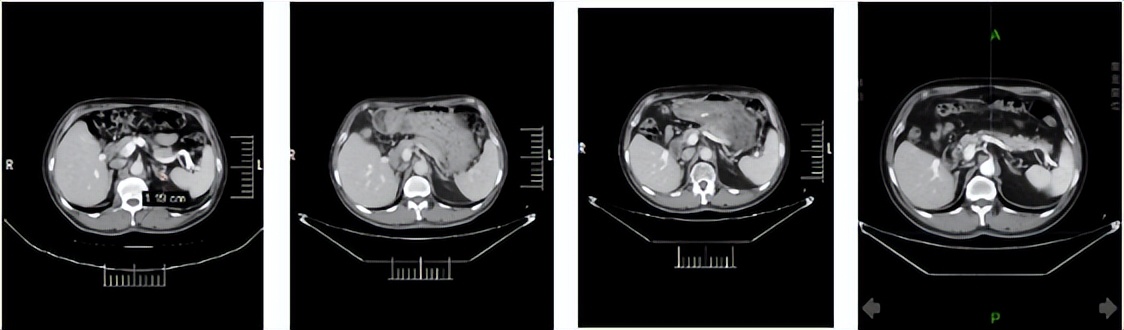

2024年1月3日:治疗4个月后,首次达到PR。

2024年5月9日,决定永久停用信迪利单抗,下调一个剂量水平(4mg,po,qd,D1-14,q3w)恢复呋喹替尼治疗。自此,截至2026年3月30日,呋喹替尼单药治疗约2年且仍在维持中。2026年3月12日行最近一次疗效评估仍处于PR,PFS已达30.4个月。

靶病灶T01:左肾下极

靶病灶T02:左肾上极

靶病灶T03:左侧肾上腺

靶病灶T04:左侧竖脊肌